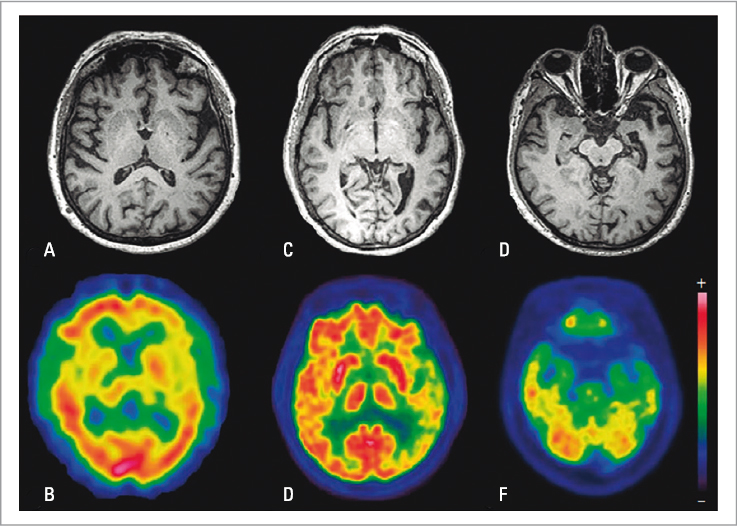

Cada variante tiene áreas específicas de atrofia y/o hipometabolismo/hipoperfusión cortical (Fig. 1), pero la naturaleza neurodegenerativa del síndrome conlleva un solapamiento evolutivo regional, correlacionado con déficits comunes4. Estos dependen de las regiones visiblemente afectadas y también de áreas sin atrofia (inicialmente indetectable) donde hay una reorganización funcional de las redes neuronales que las conectan con las regiones atróficas mediante tractos de sustancia blanca. A pesar del solapamiento, en todas las variantes se mantiene la asimetría izquierda, y por tanto, la afectación intrahemisférica10.

FIGURA 1. Cortes axiales de resonancia magnética y tomografía por emisión de positrones cerebral de un paciente con la variante agramatical/no fluente de afasia primaria progresiva (A,B), la variante logopénica (C,D) y la variante semántica (E,F). Se muestran las regiones típicamente afectadas según los criterios de neuroimagen vigentes de apoyo al diagnóstico clínico (consúltese la Tabla 1) (tomada de Gil-Navarro et al., 2013 9).